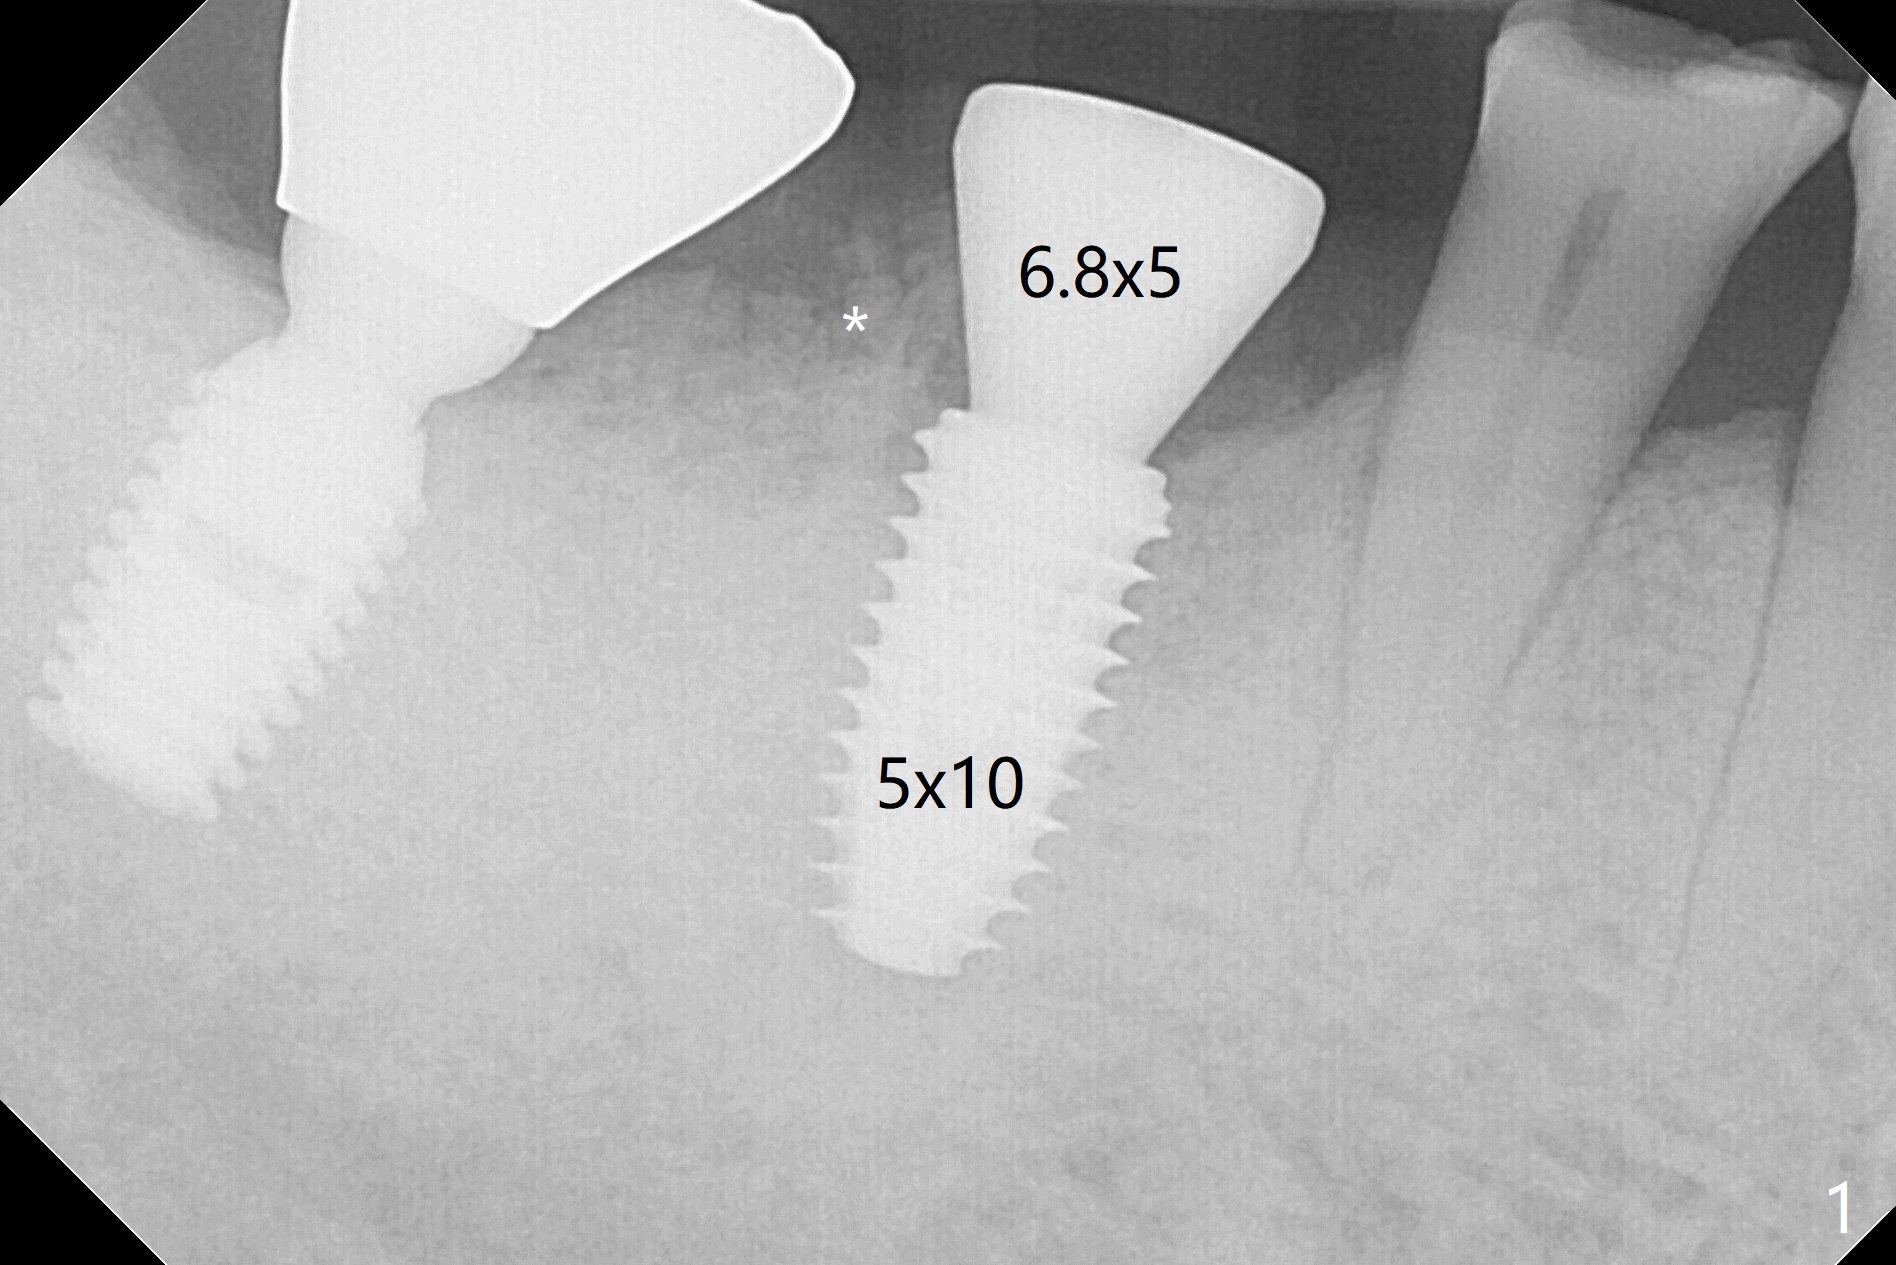

M

Vertical fracture of the mesial root of the tooth #30 after RCT is associated with bone loss (Fig.00 *). When the mesial portion of the mesial root (M', loose one) is exfoliated, the bone loss resolves (Fig.0). To reduce heat-induced bone necrosis at #19, osteotomy is conducted slowly with copious irrigation with cold saline. Bone density is felt while a 5x10 mm implant is being placed after using cortical tap to the 2nd line of the implant driver. The implant needs to be reverse torqued several times before reaching its final depth (Fig.1 (~50 Ncm)). Since the residual roots are superficially positioned, the immediate implant looks as a delayed one. Although the implant is placed mesial to the septum clinically, its position in X-ray seems to be normal. Because of severe wear and lack of vertical height, a 6.8x5 mm healing abutment is placed. Retention of bone graft (Fig.1 *) is maintained by spreading setting acrylic into the edentulous undercut areas (Fig.2 *). The so called "acrylic dressing" remains in place 3 weeks postop (Fig.8). When it is removed with the healing abutment, the wound heals (Fig.3). Note the limited vertical height. The bone graft placed in the distal socket appears to have been converted to the native bone 3.5 months postop (Fig.4). To reduce severe wear of the natural teeth, the occlusion of the new crown is not heavily decreased (Fig.5). It should be alright considering favorable crown/implant ratio (Fig.6). There is no bone loss 5 months post cementation, although the abutment screw is just retightened (Fig.7). In spite of poor trajectory associated with #18 (Fig.8) and 31 (Fig.7) Bicon implants, the abutments have not been dislodged. For the bruxer, the next implant at #19 with distal root fracture (Fig.8 ^) should be Bicon. The patient complains of food impaction nearly 1 year post cementation. The mesial and distal contacts of #30 crowns are light. When the abutment/crown is removed, there is implant well contamination (food debris). It appears that the previous abutment (5.7x4(2) mm, Fig.6,7) is incompletely seated. When a smaller abutment is placed and torqued at 30 Ncm, it is seated fully (Fig.9 (<: no gap)). New impression is taken. The distal gingival embrasure is larger than the mesial one because of the higher distal crest (Fig.6,7). If there is food impaction distal to the new crown, the distal crestal bone should be removed with lab closure of the embrasure.